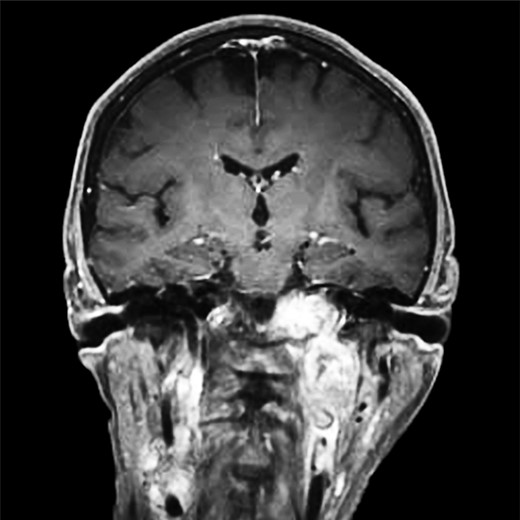

Repeat magnetic resonance imaging (Figs. 3 and 4) showed increased left-sided carotid PGL, significant extension into the jugular foramen and skull base, and associated high-grade tumor compromise of the left internal carotid artery; no radiologic evidence suggested intracranial ischemic sequelae. Computed tomographic (CT) imaging showed infiltration of the left petrous and clivus regions of the skull (Fig. 5). Findings were compatible with progression of the previously known tumor.

Magnetic resonance angiogram, coronal plane, shows tumor compromise of the left internal carotid artery.